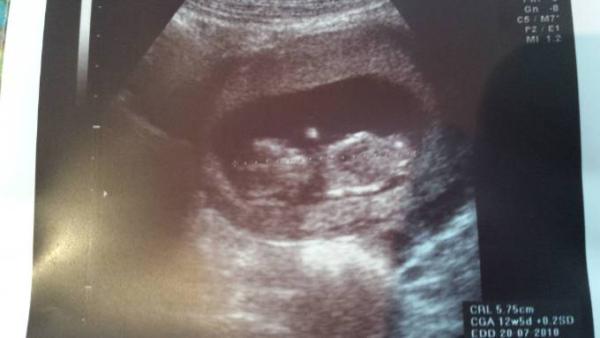

Hey :) Ich hatte Ultraschall heute und alles sieht gut aus. Herzchen schlägt und Zwerg ist ordentlich gewachsen Ich hab ja bis zum Schluss überlegt, ob ich das ETS mache, aber hab mich dann dagegen entschieden. Es gibt für mich eigentlich keinen Grund dafür, und Wahrscheinlichkeiten bringen mich eh nicht weiter. Euch alle einen schönen Tag, kommt gut durch den Sturm und passt auf euch auf! Hier noch das Bildchen:

Bild zu Auch zurück vom Arzt - Forum für Juli - Mamis

Sehr schön das freut mich < 3 Da hast du ja ein super Bild bekommen. Wie groß ist denn dein Bauchzwerg jetzt?